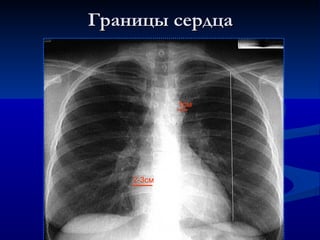

Границы сердца 2-3см 1см

Кардиоторакальный индекс Норма  –  50% Кардиомегалия  –  >  5 0 % VD VS Thorax VD+VS /  0.5 Thorax